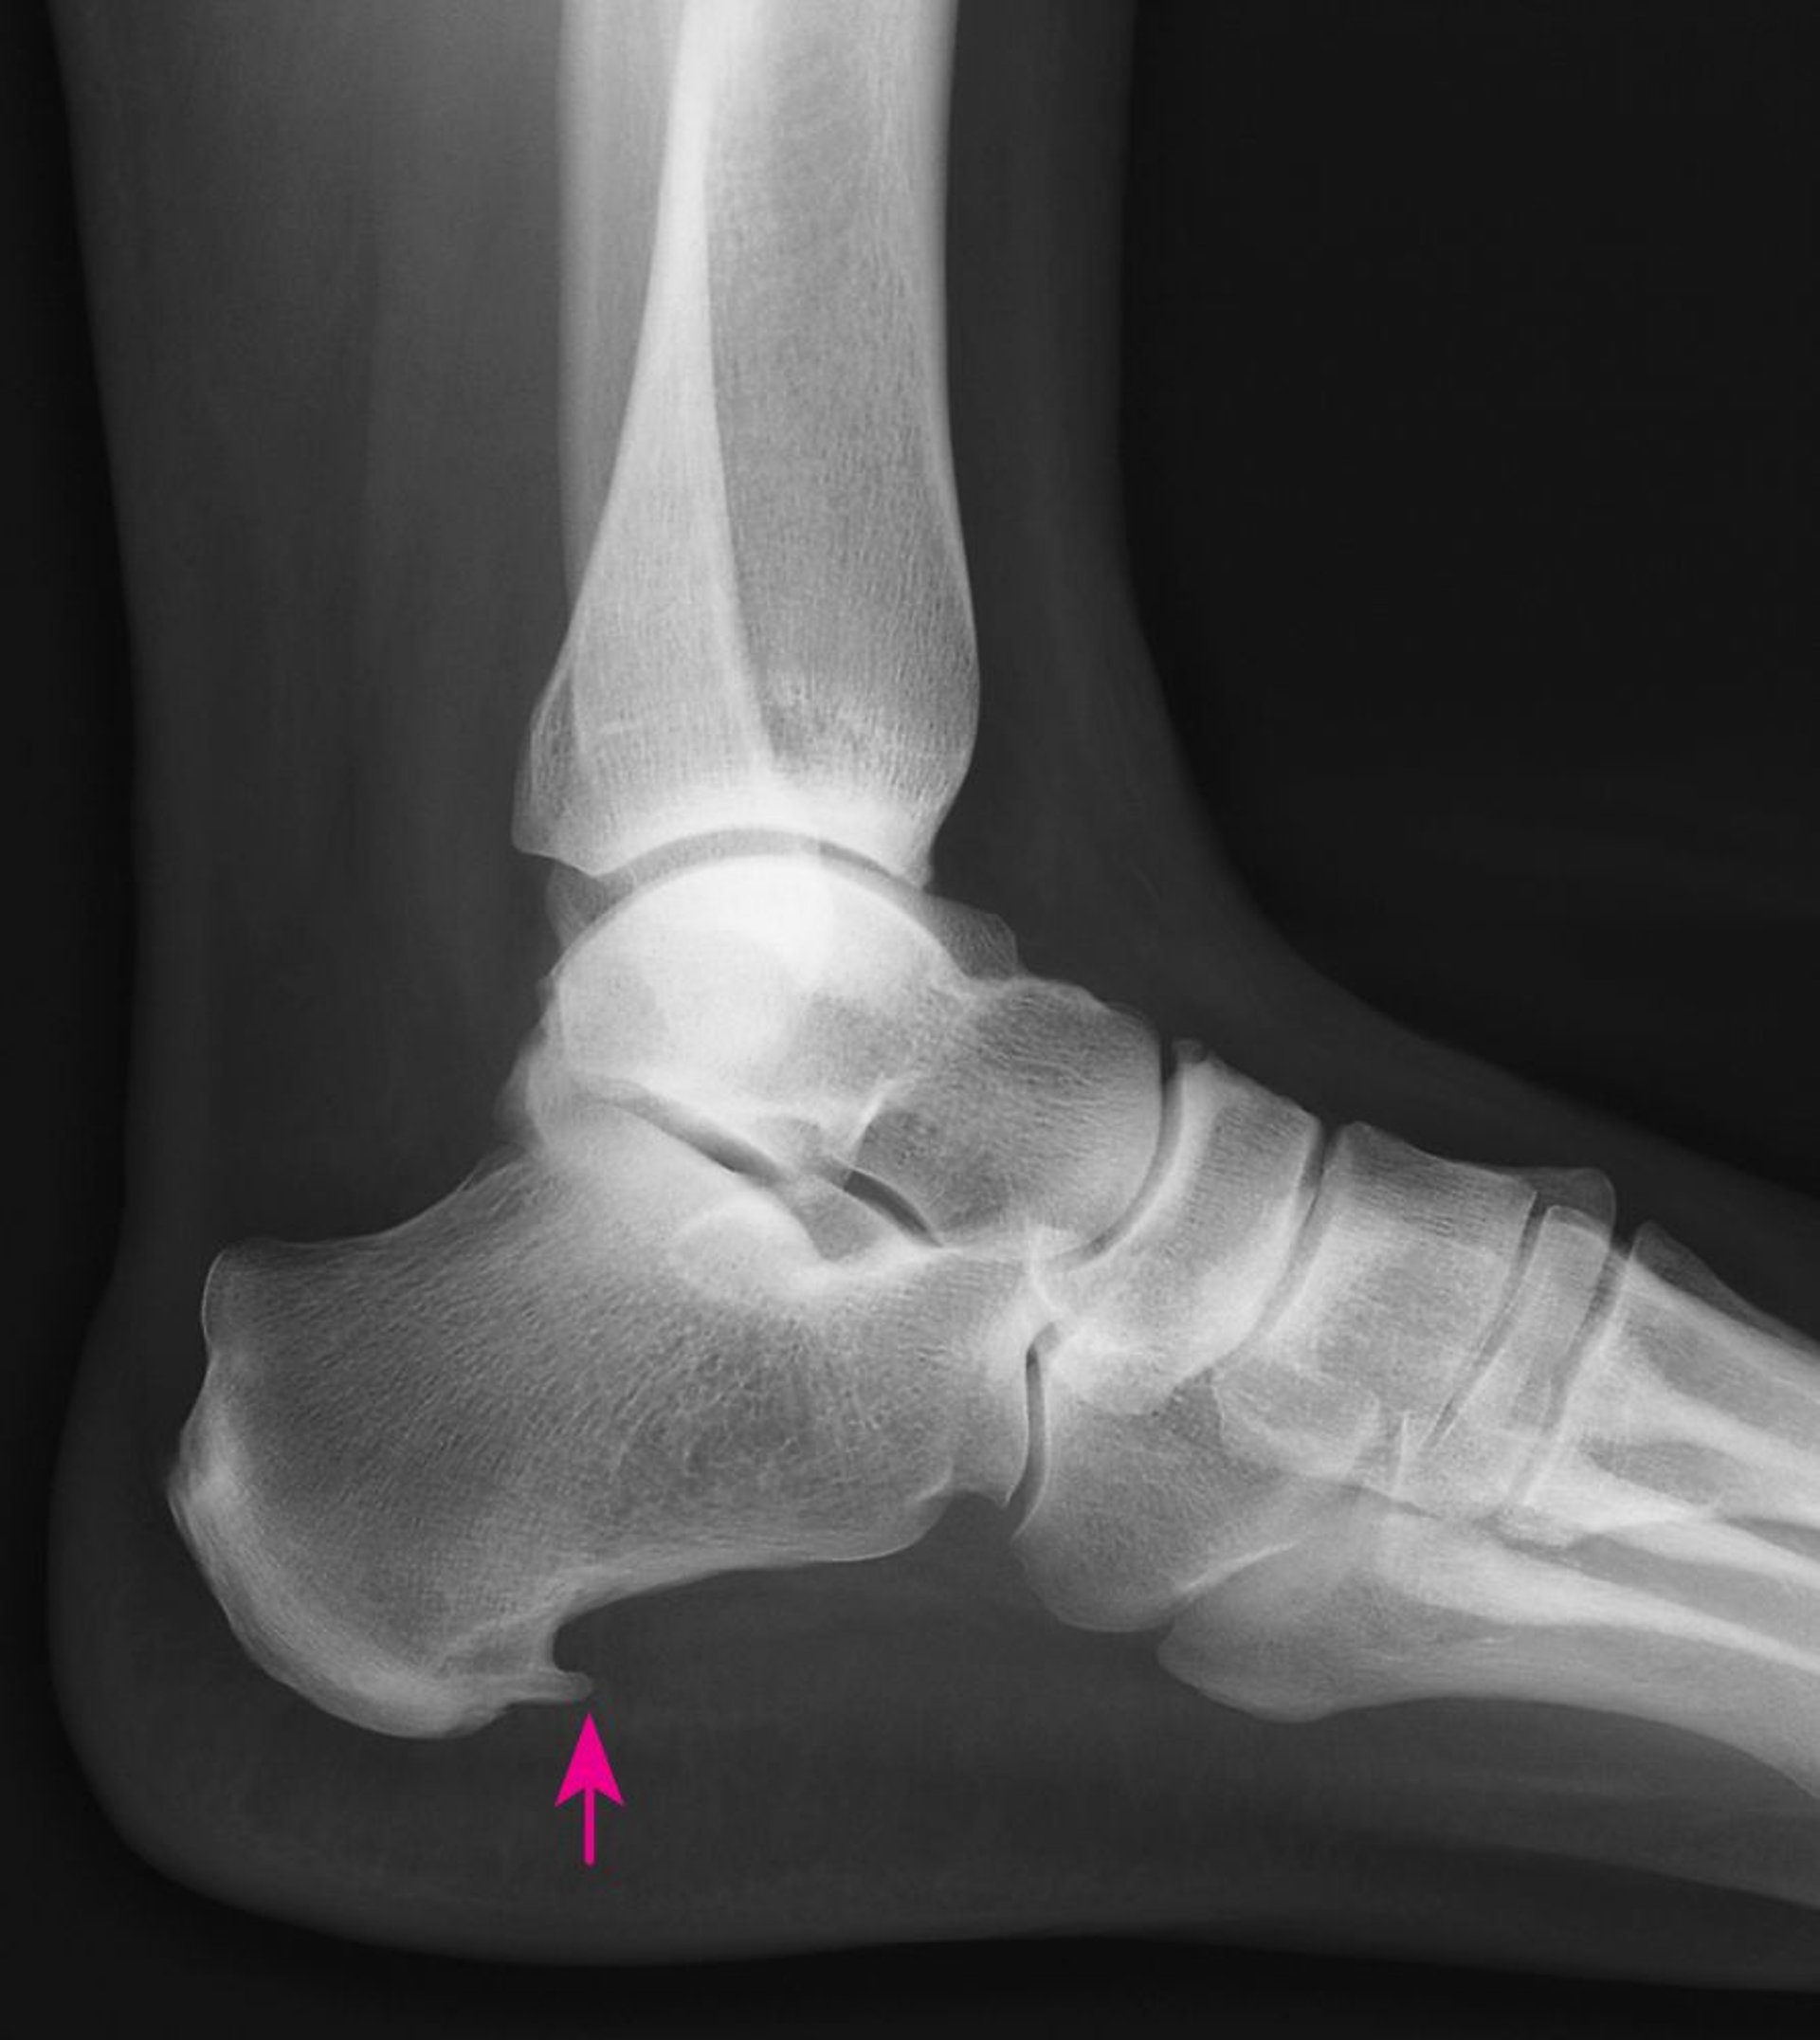

एक्स-रे एड़ी की हड्डी के निचले भाग की आगे वाली किनारे से उठी हुई एड़ी की कील को दिखा सकते हैं। हालांकि, प्लैंटार फ़ैसाइटिस से पीड़ित लोगों को अक्सर हील स्पर्स नहीं होती और हील स्पर्स होने से पीड़ित अधिकतर लोगों को दर्द नहीं होता, इसलिए हील स्पर्स होने का मतलब यह नहीं होगा कि प्लैंटार फ़ैसाइटिस की उपस्थिति भी अवश्य होगी और साथ ही इसका अर्थ यह भी नहीं होता कि हील स्पर्स का इलाज करने की आवश्यकता है।